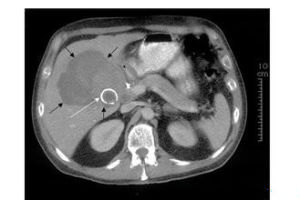

Mirizzi綜合徵的臨床表現複雜,無特異性,實驗室檢查也無特異性的指標,影像學診斷的檢出率亦很低,客觀上造成術前對Mirizzi綜合徵的低確診率。對於有黃疸史的膽囊結石患者均應考慮有Mirizzi綜合徵的可能,實驗室檢查肝功能異常,如血清膽紅素、AST、AKP升高,B超表現萎縮性膽囊、“三管征”或ERCP、MRCP上見到膽囊管過長或膽囊管與肝總管並行,“反C征”要高度懷疑Mirizzi綜合徵。

3.CT檢查;